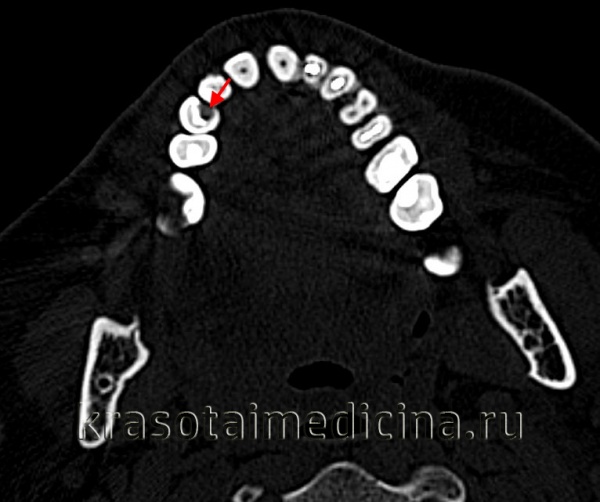

Рецидивирующий кариес (вторичный кариес, кариес пломбированного зуба). Рецидивирующий кариес развивается вблизи пломбы. Он свидетельствует о наличии серьёзных кариесогенных факторов риска, недостаточном уходе за полостью рта или неполноценного лечения первичного кариеса. Рецидивирующий кариес начинается вблизи края пломбы, кариозный очаг имеет тёмный цвет и мягкую консистенцию при зондировании. При рентгенологическом исследовании выявляют два типа диаметрально противоположных изменений. При одном типе разрушение твёрдых тканей зуба проявляется в виде очага просветления под пломбой, край которой может иметь дефект.

В случае, представленном на рисунке, этот дефект располагается под амальгамной пломбой, установленной на дистальной поверхности второго нижнего премоляра. При втором типе изменений очаг поражённой ткани зуба имеет повышенную рентгеноконтрастность, расположен под ранее поставленной пломбой и по форме напоминает языки пламени или наконечник стрелы, который остриём направлен к пульпе, и может проникать в полость зуба. На рисунке описанные изменения можно увидеть под амальгамной пломбой на мезиальной поверхности первого нижнего моляра. Иногда, как и в представленном случае, одновременно отмечают очаг просветления. Ткань повышенной рентгеноконтрастности при спектроскопическом исследовании представляет собой уплотнённый дентин, который пропитался цинком из соседней амальгамной пломбы. Лечение рецидивного кариеса заключается в удалении старой пломбы и повторном пломбировании обработанной полости.